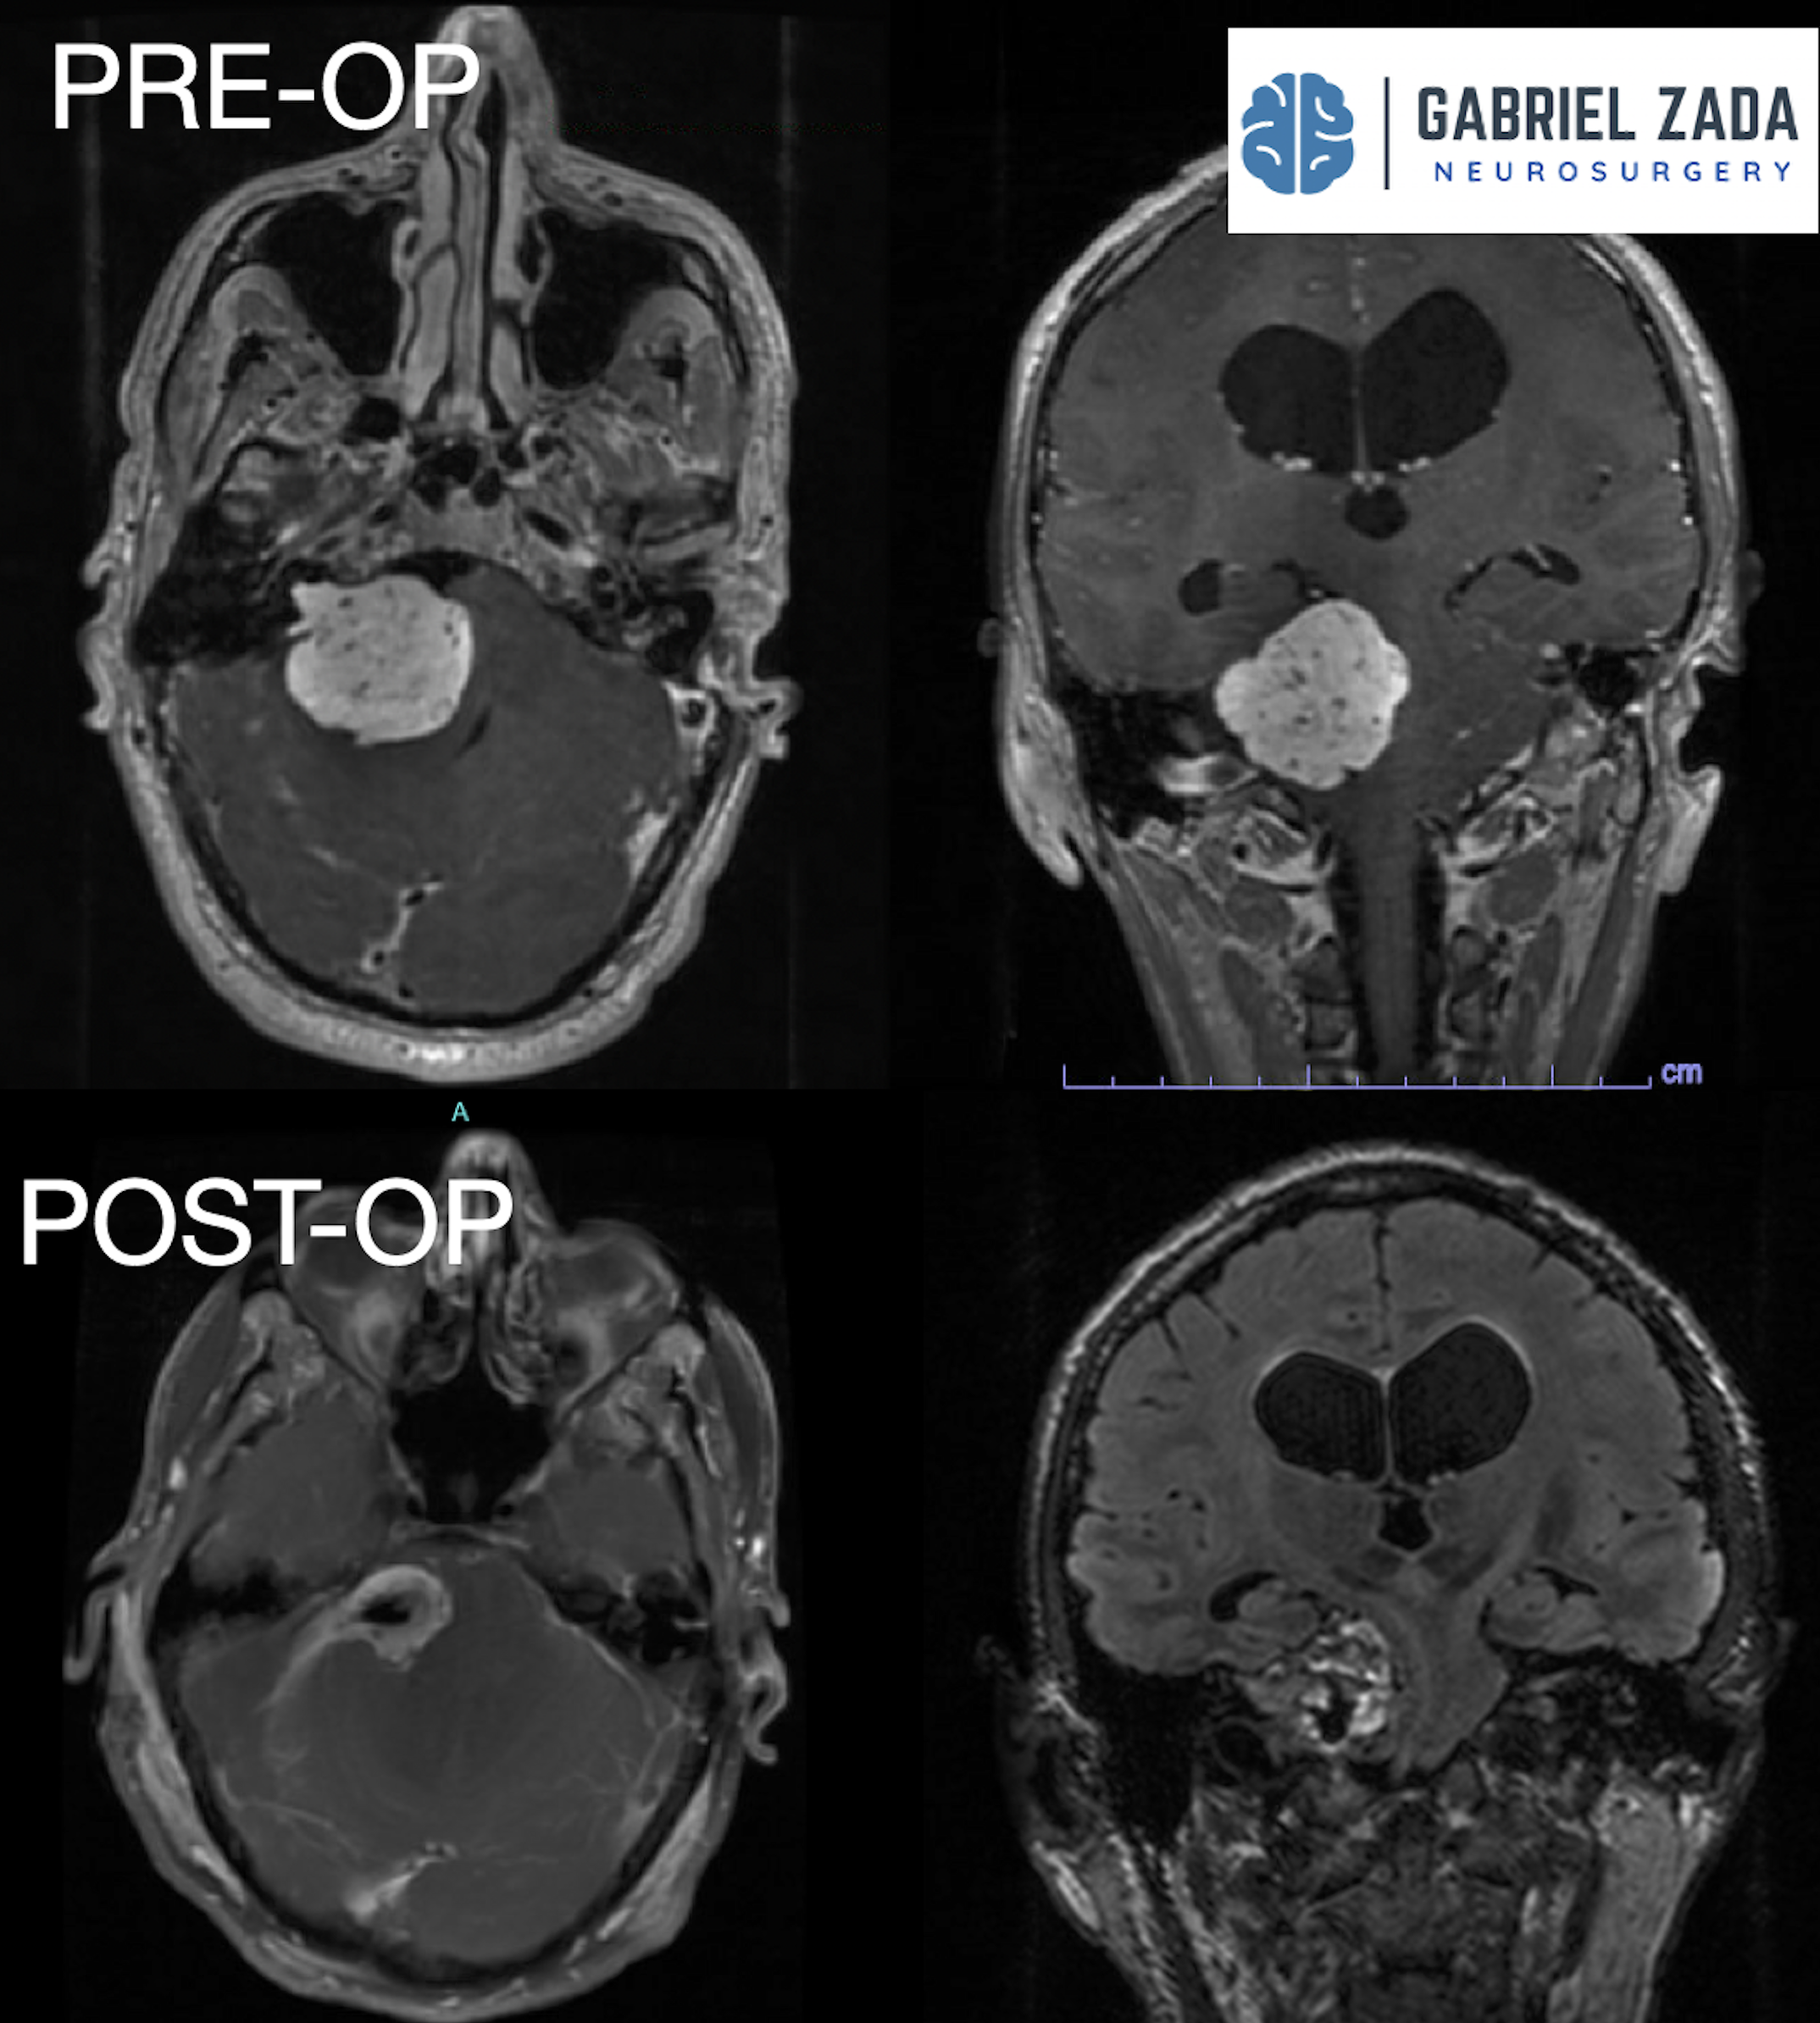

Explore this comprehensive gallery featuring pre‑ and post‑operative imaging of patients with skull‑base tumors treated by Gabriel Zada, MD, MS, FAANS, FACS. These cases highlight Dr. Zada’s expertise in advanced neurosurgical techniques and outcomes.

*Representative cases shown for educational purposes. All images de-identified. Individual results vary.